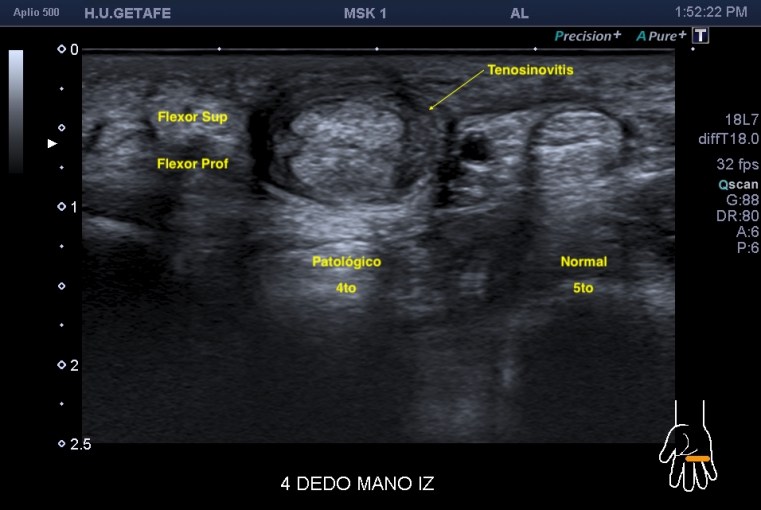

En la imagen 2 la imagen resulta fantástica, detente a estudiarla, coexiste normalidad del 5to dedo en eje corto y el 4to dedo afectado por una inflamación en su vaina que lo envuelve como una circunferencia marcando la anatomía de ambos flexores manera increíble. La imagen 3 es para que disfrutes de la anatomía sin letreros, es espectacular.